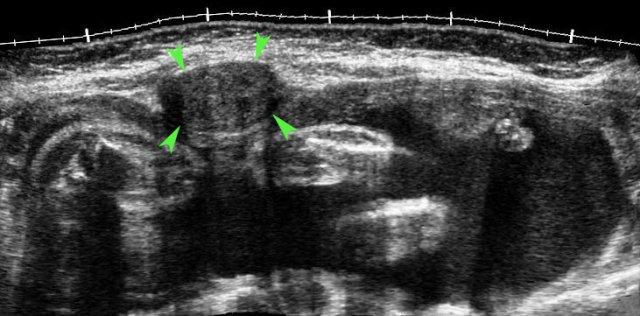

PID ca lâm sàng 4

Các hình ảnh này của một phụ nữ trẻ bệnh nặng, đau nhiều với viêm phúc mạc toàn thể và CRP 250, nghi ngờ lâm sàng là thủng ruột thừa.

Siêu âm cho thấy ruột non mất nhu động (b.).

Không quan sát được ruột thừa.

TVUS cho thấy tử cung bình thường và buồng trứng bình thường (đầu mũi tên), được bao quanh bởi mô tăng âm (*).

CT xác nhận hình ảnh liệt ruột và ruột thừa bình thường (mũi tên).

PCR dương tính với lậu cầu.